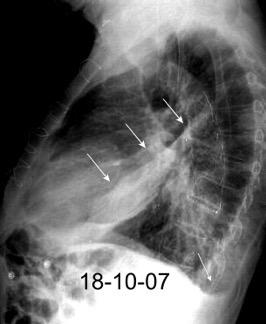

Marzo 2014: Perforación longitudinal distal secundaria a episodio de vómito (síndrome de Boerhaave). Derrame pleural izdo. que evoluciona a empiema.

Wang C-T et al. Tension hydropneumothorax in a Boerhaave syndrome patient: A case report . World J Emerg Med, 2021. Katabathina V et al. Nonvascular, nontraumatic mediastinal emergencies in adults:a comprehensive review of imaging findings. Radiographics. 2011.